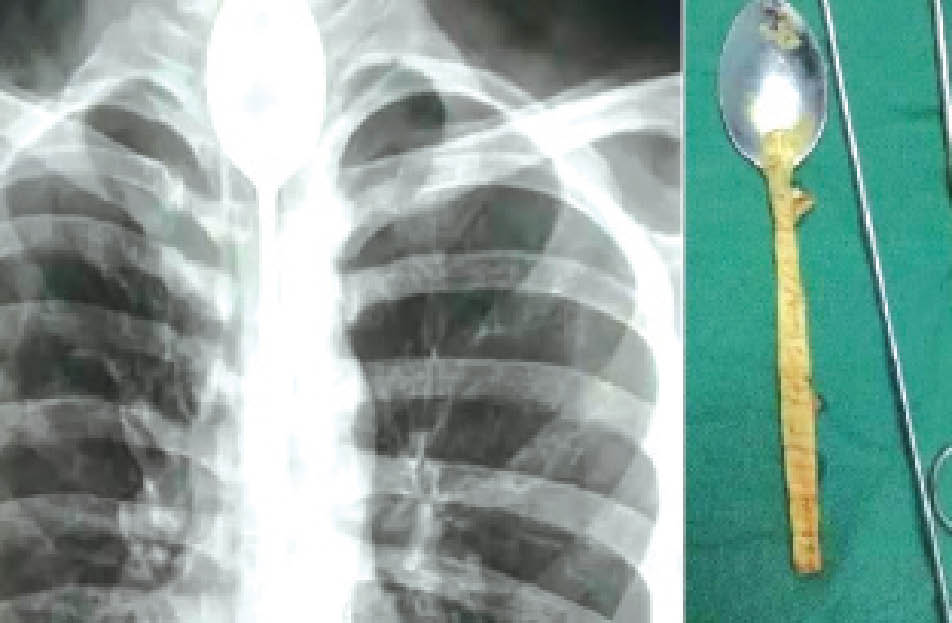

وقام بإبتلاع ملعقة معدنية يبلغ طولها 20 سنتيمتراً، ولم يفلح في إخراجها، وبقيت عالقة داخل المريء عاماً كاملاً دون أن تعيقه عن الأكل والشرب بشكل طبيعي، حسب ما ذكر موقع (ديلي ميل) البريطاني.

ومنذ أيام، تعرض الشاب لضربة في صدره، شعر بعدها بآلام وصعوبة في التنفس دفعته للذهاب إلى مستشفى في مقاطعة شينجيانغ الصينية، حيث اكتشف الأطباء وجود الملعقة، التي تسببت بالتهاب في المريء.

وقام الأطباء بإخراج الملعقة عبر تقنية المنظار، مستخدمين أداة تم إدخالها عن طريق الفم، لتلتقط الملعقة وتخرجها، في عملية إستغرقت ساعتين.